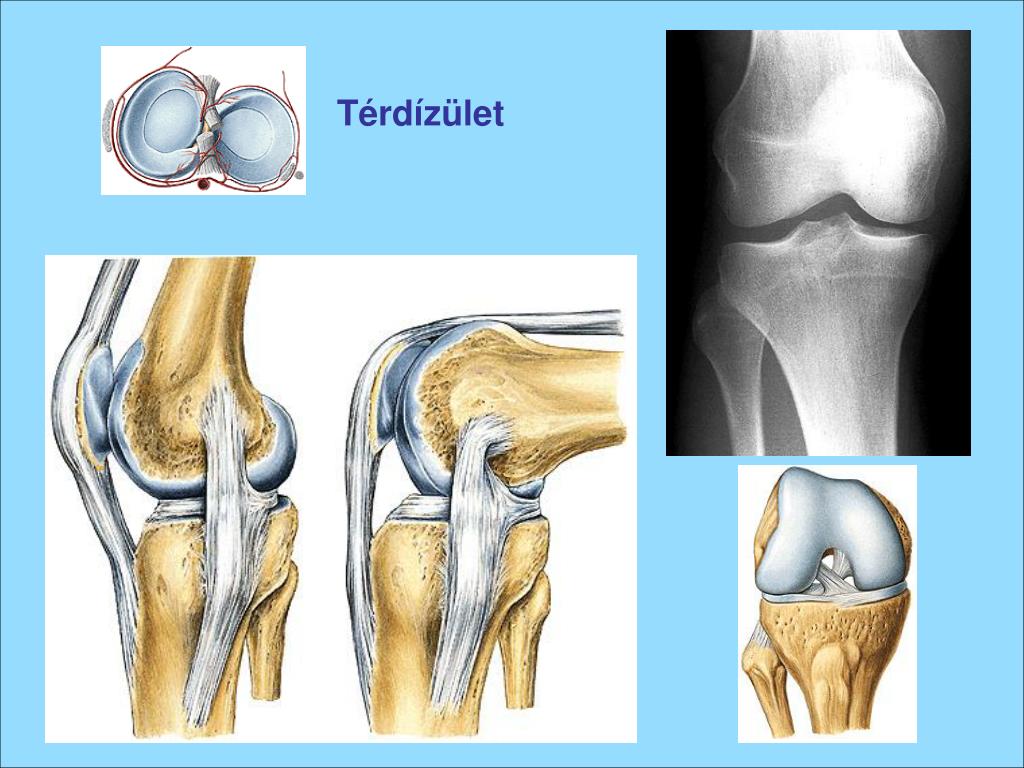

22. Térdízület • combcsont • sípcsont = tibia • szárkapocscsont = fibula • térdkalács = patella • meniscusok (2 db félhold alakú porc) • oldal & keresztszalagok

23. Térdízület